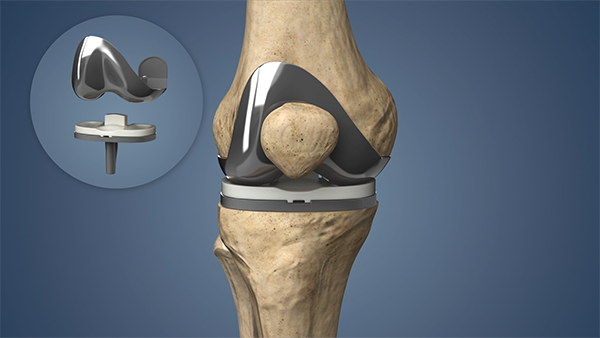

Au cours de l’intervention, les surfaces cartilagineuses et osseuses endommagées du genou sont remplacées par des composants prothétiques conçus pour rétablir l’alignement, la stabilité et la mobilité de l’articulation. Le remplacement total du genou est envisagé lorsque la douleur et la raideur affectent de manière significative les activités quotidiennes et la qualité de vie, et lorsque les traitements non chirurgicaux ne sont plus efficaces.

Le remplacement total du genou comprend :

L’intervention est réalisée à l’aide de techniques chirurgicales éprouvées et fondées sur les données scientifiques. Le choix de la prothèse et de l’approche chirurgicale dépend de l’anatomie du patient, de sa condition et de son état de santé général.